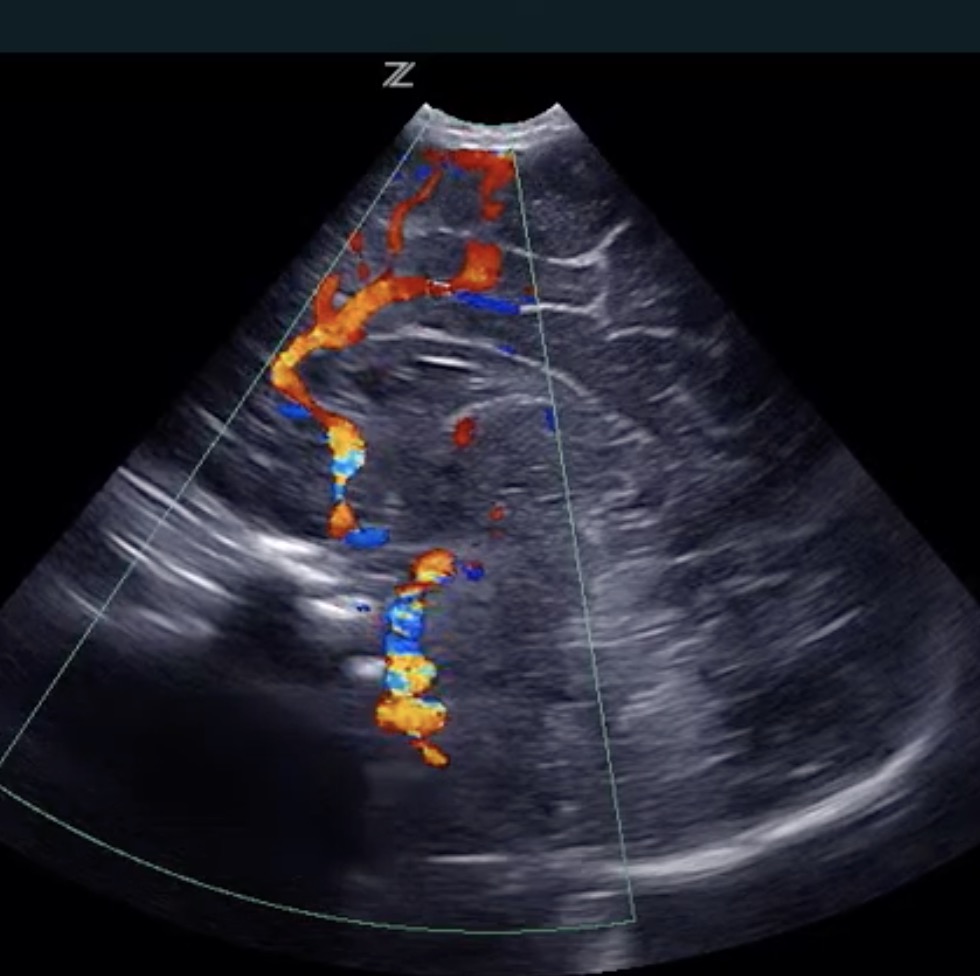

Advanced Acoustic Acquisition (AAA) is a software-based data acquisition method that captures up to 90% of the returning acoustic data and then processes it up to 10x faster by interrogating a relatively smaller number of large zones and extracting more information from each acquisition. Conventional ultrasound systems can capture only a few receive data sets from each transmit event due to processing time requirements for each data set which creates an acoustic acquisition backlog that results in processing constraints. This inherent limitation is overcome by using a flexible, software-based channel domain processor.